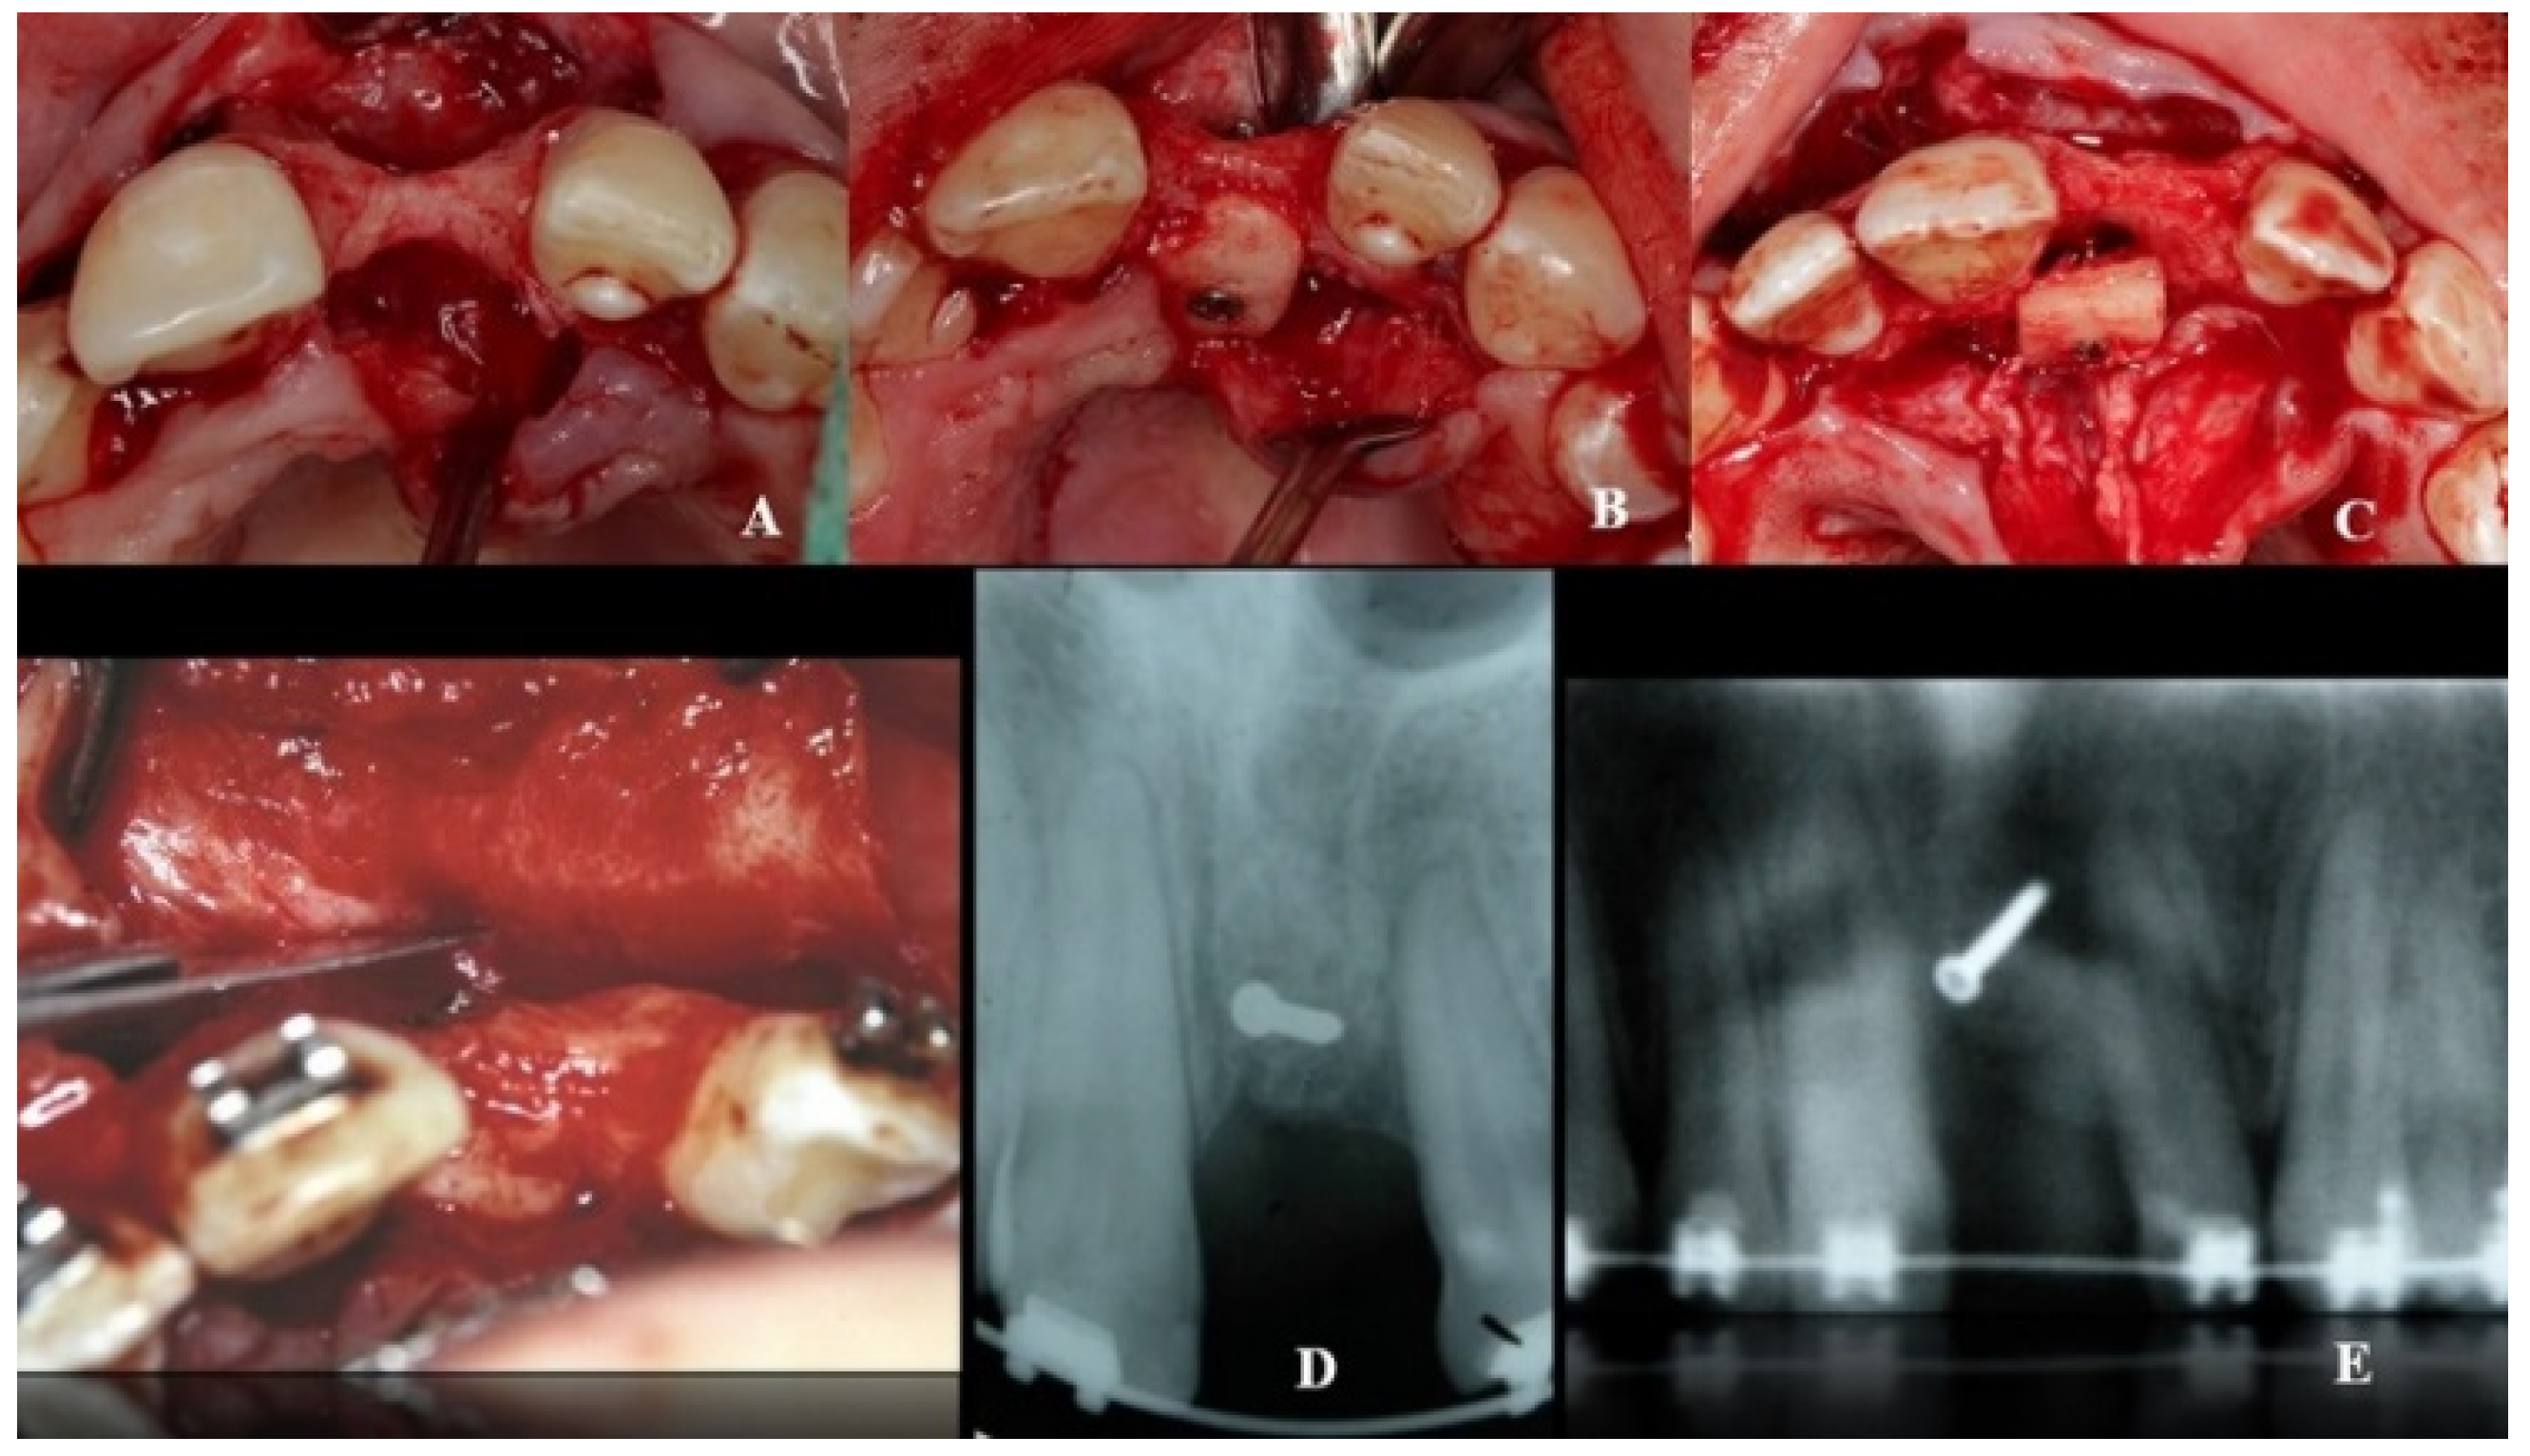

A double approach was used on the recipient jaw. On its vestibular aspect, compensating incisions were made distally on the lateral incisors (1.2 and 2.2), joined by an intrasulcular incision at the level of teeth 1.2 to 2.2, including a central incisor. A crestal incision was traced over the toothless residual ridge. A full-thickness trapezoidal flap was obtained upon curettage. On the palatal side, extensive curettage was performed to obtain a pocket covering the area from 1.2 to 2.2, thus exposing the bone defect and revealing the neurovascular bundle. The latter was next emptied with a bone scraper, and a 20 mm wide × 10 mm high cortico-cancellous block was obtained and placed palatally, covering the incisor foramen to increase the vestibulo–palatal width of the residual ridge. The blocks were held in position by titanium fixation micro-screws (BoneScrew kit® BioHorizons, Birmingham AL, USA) (Figure 4).

Figure 4.

Recipient area (A). Location of the bone block at the level of the foramen incisive (B) and on its incisal aspect (C). (D,E) Block fixation using fixing screws.

Combined application of autogenous bone and a xenograft (BioOss, Geistlich-Pharma AG, Schlieren, Switzerland) was then performed on the palatal, crestal, and vestibular aspects of the defect and canal areas, in order to increase the contour. A resorbable type I collagen membrane (Mem-Lok® RCM, BioHorizons, Birmingham, AL, USA) was then placed on the site, folded to cover the enlarged area, and attached with additional titanium tacks on the buccal side.

During the second surgery, 6 to 10 months thereafter, the fixation screws were removed. With the help of a surgical guide, Tapered Internal Laser-Lok® 3.8 implants with a 3.5 mm prosthetic platform (BioHorizons, Birmingham, AL, USA) were positioned in the correct 3D position. Provisional restoration consisted of an acrylic crown attached to the teeth adjacent to the gap with an adhesive system (Figure 5).

Figure 5.

With the help of a surgical guide, implants were positioned in the correct 3D position.